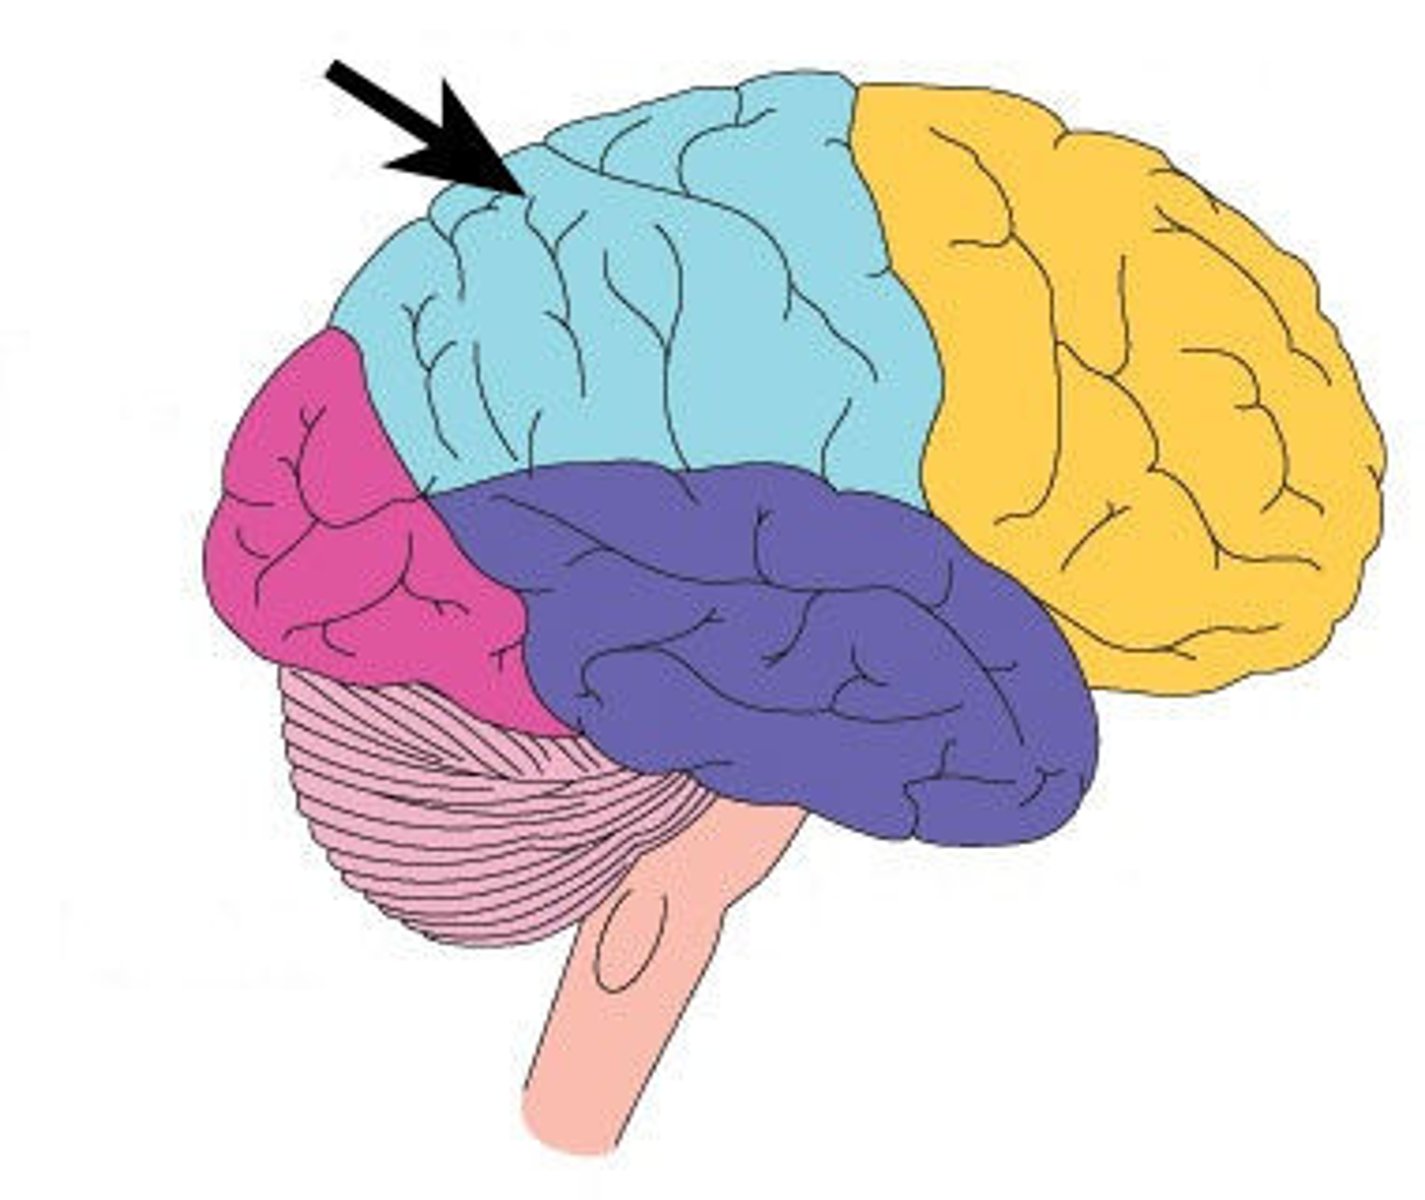

Surface lobes of the cerebrum

Frontal Lobe,

Temporal Lobe,

Parietal Lobe,

Occipital Lobe

Frontal Lobe

Primary (somatic) motor cortex

Temporal Lobe

Olfactory and Auditory input

Parietal Lobe

Reception and evaluation (integration) of sensory information except for smell, hearing, and vision

Occipital Lobe

Vision and integration of visual input